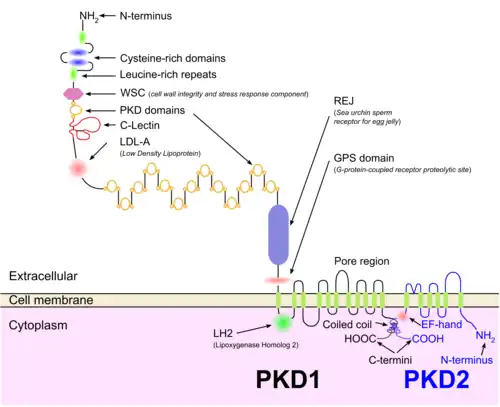

Genetic mutations in any of the three genes PKD1, PKD2, and PKD3 have similar phenotypical presentations.[15]

- Gene PKD1 is located on chromosome 16 and codes for a protein involved in cell cycle regulation and intracellular calcium transport in epithelial cells and is responsible for 85% of the cases of ADPKD.[16]

- Gene PKD2 is identified, using genetic linkage study,[17][18] on chromosome 4.[19] A group of voltage-linked cation channels, with inward selectivity for K>Na>>Ca and outward selectivity for Ca2+ ≈ Ba2+ > Na+ ≈ K+, are coded for by PKD2 on chromosome 4.[20]

Both autosomal dominant and autosomal recessive polycystic kidney disease cyst formation are tied to abnormal cilia-mediated signaling. The polycystin-1 and polycystin-2 proteins appear to be involved in both autosomal dominant and recessive polycystic kidney disease due to defects in both proteins.[21] Both proteins communicate with calcium channel proteins, and cause a reduction in resting (intracellular) calcium and endoplasmic reticulum storage of calcium.[22]